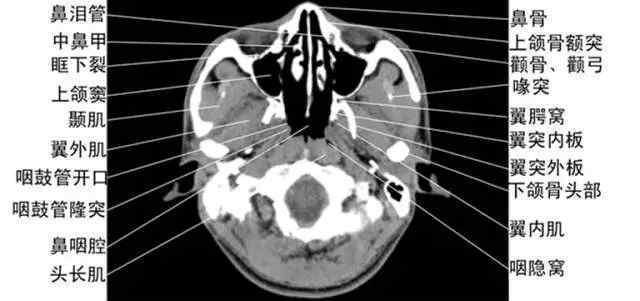

收集全身ct图谱。

中国医学网提供图像学习专题,帮助您快速学习如何阅读电影。综合讲解:胸像,脑像,腹像,骨科像…